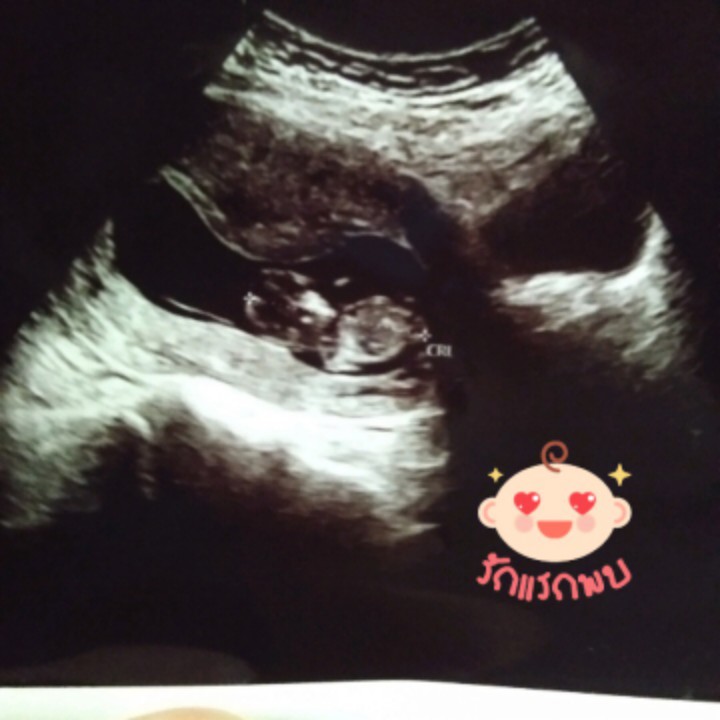

12w

Post reply image